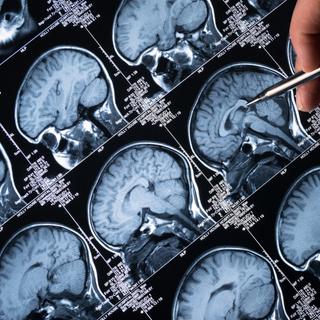

O cérebro humano é um órgão que consome muita energia: embora represente apenas cerca de 2% do peso do corpo, consome quase 20% da energia total produzida pelo corpo. Esta energia é fornecida por um pequeno molécula essencial chamado NAD+. Com a idade, os níveis de NAD+ diminuem naturalmente, tornando as células menos eficientes nas suas funções vitais.

NAD+ é uma molécula essencial que permite que as células cerebrais produzam energia e se reparem. O estudo sugere que restaurar o equilíbrio do NAD+ poderia ajudar o cérebro a recuperar certas funções prejudicadas pela doença de Alzheimer. © MclittleStock, Adobe Stock